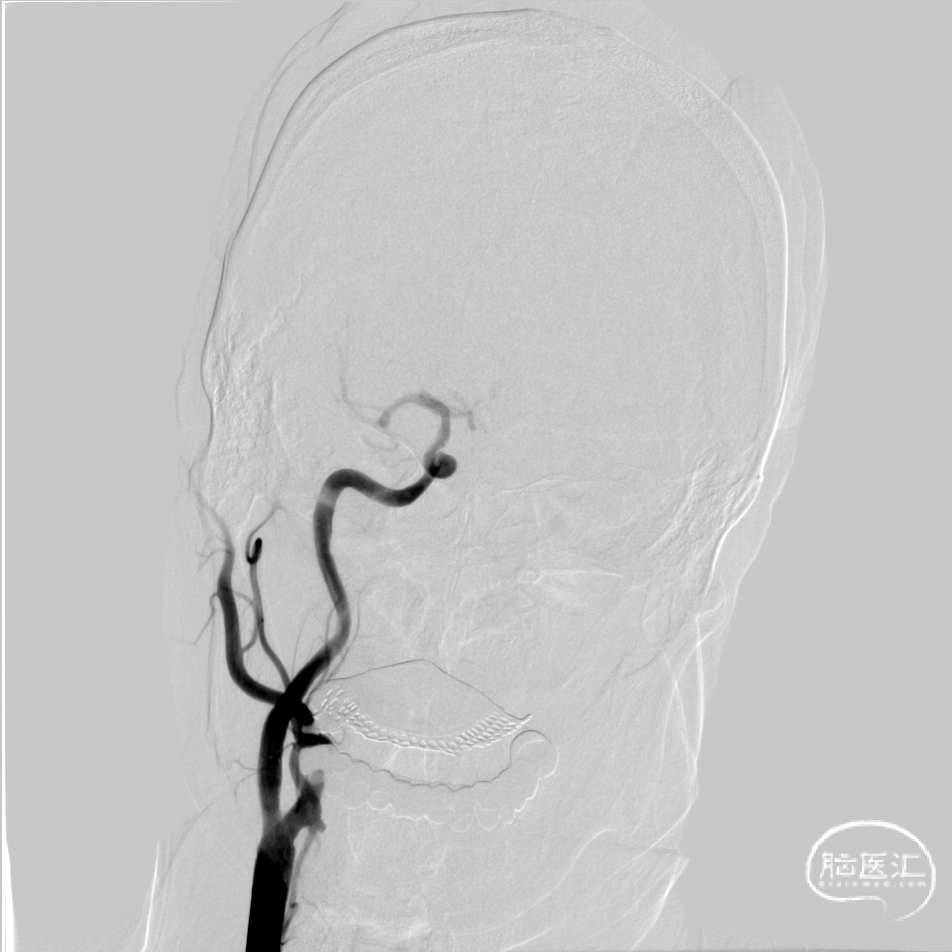

术前右侧颈总动脉造影示颈内动脉起始段次全闭塞

术后造影-重度狭窄70%,远端血流速度明显改善。

术前术后对比。